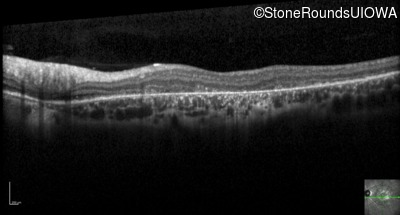

Optical Coherence Tomography - Right - 20/200 -3

Exemplar / OCT Stack

OCT Stack